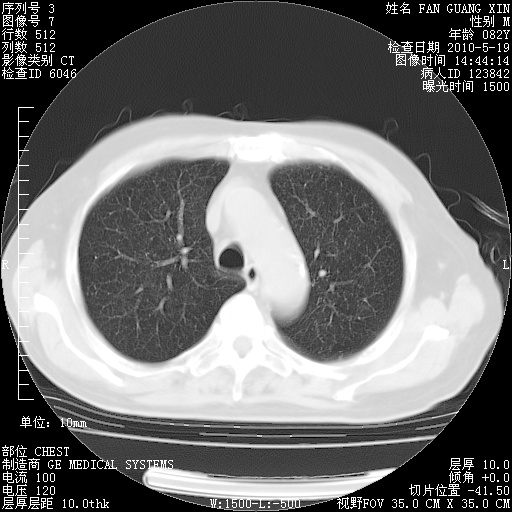

复查肺部CT,明显好转。为什么发热呢?

治疗3周后的肺部CT